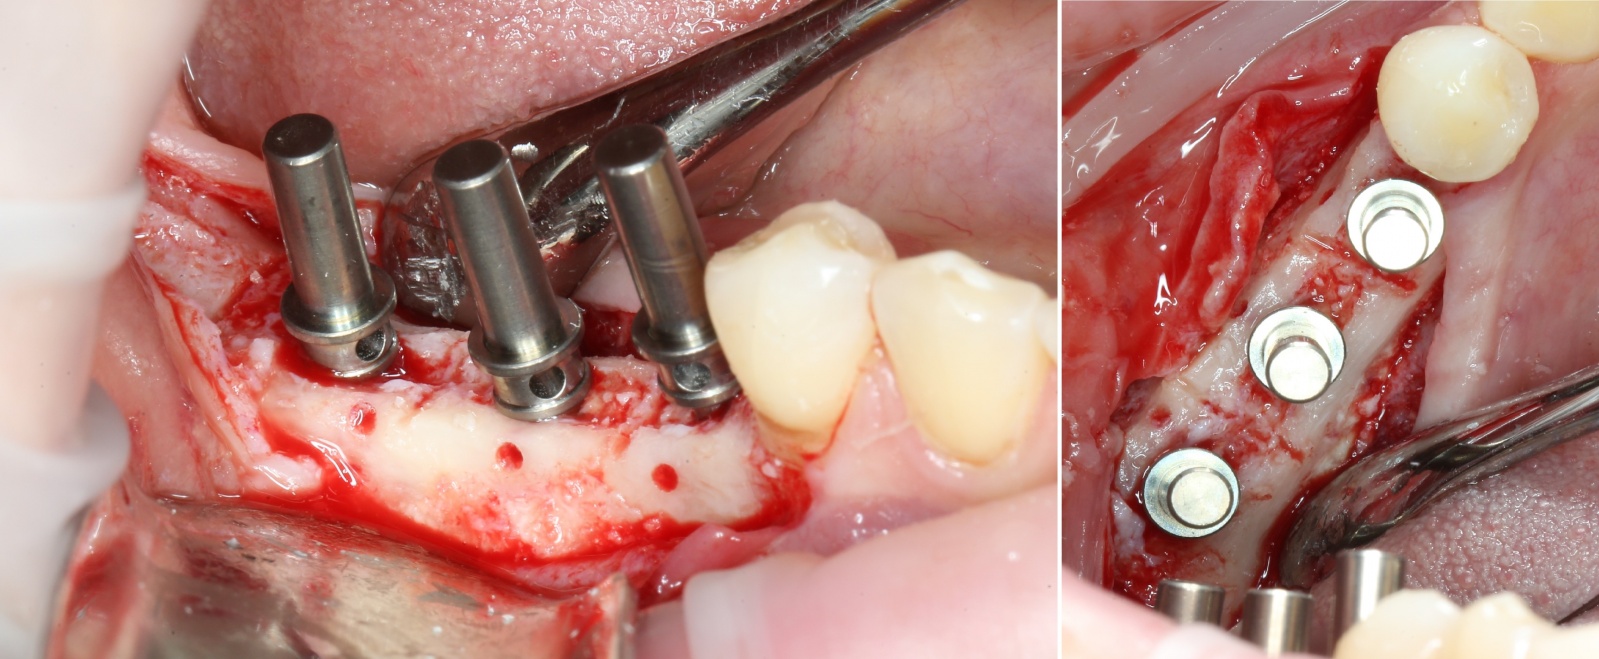

Для фиксации костного фрагмента, чтобы тот в дальнейшем не отвалился, используются специальные винты.

С учётом того, что это не саморезы, для начала необходимо сделать отверстия в кости:

Для этого используется прямой наконечник и фрезы разного диаметра (охлаждение производится при помощи физ. раствора, который подается через трубку):

Берём отвертку и вкручиваем винтики:

Получаем вот такой короб:

Вкратце, при помощи пинов проводится проверка параллельности:

Устанавливаются имплантаты:

И «глушатся»: